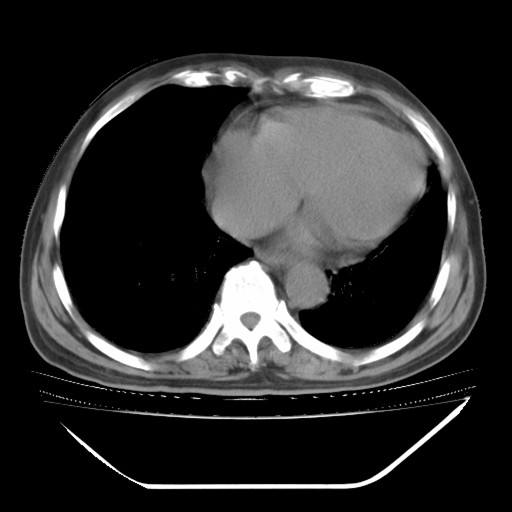

以下是引用hhcckk在2009-5-29 10:34:00的发言:[br]左下肺片絮状边缘模糊影,考虑感染,建议治疗后复查[br]